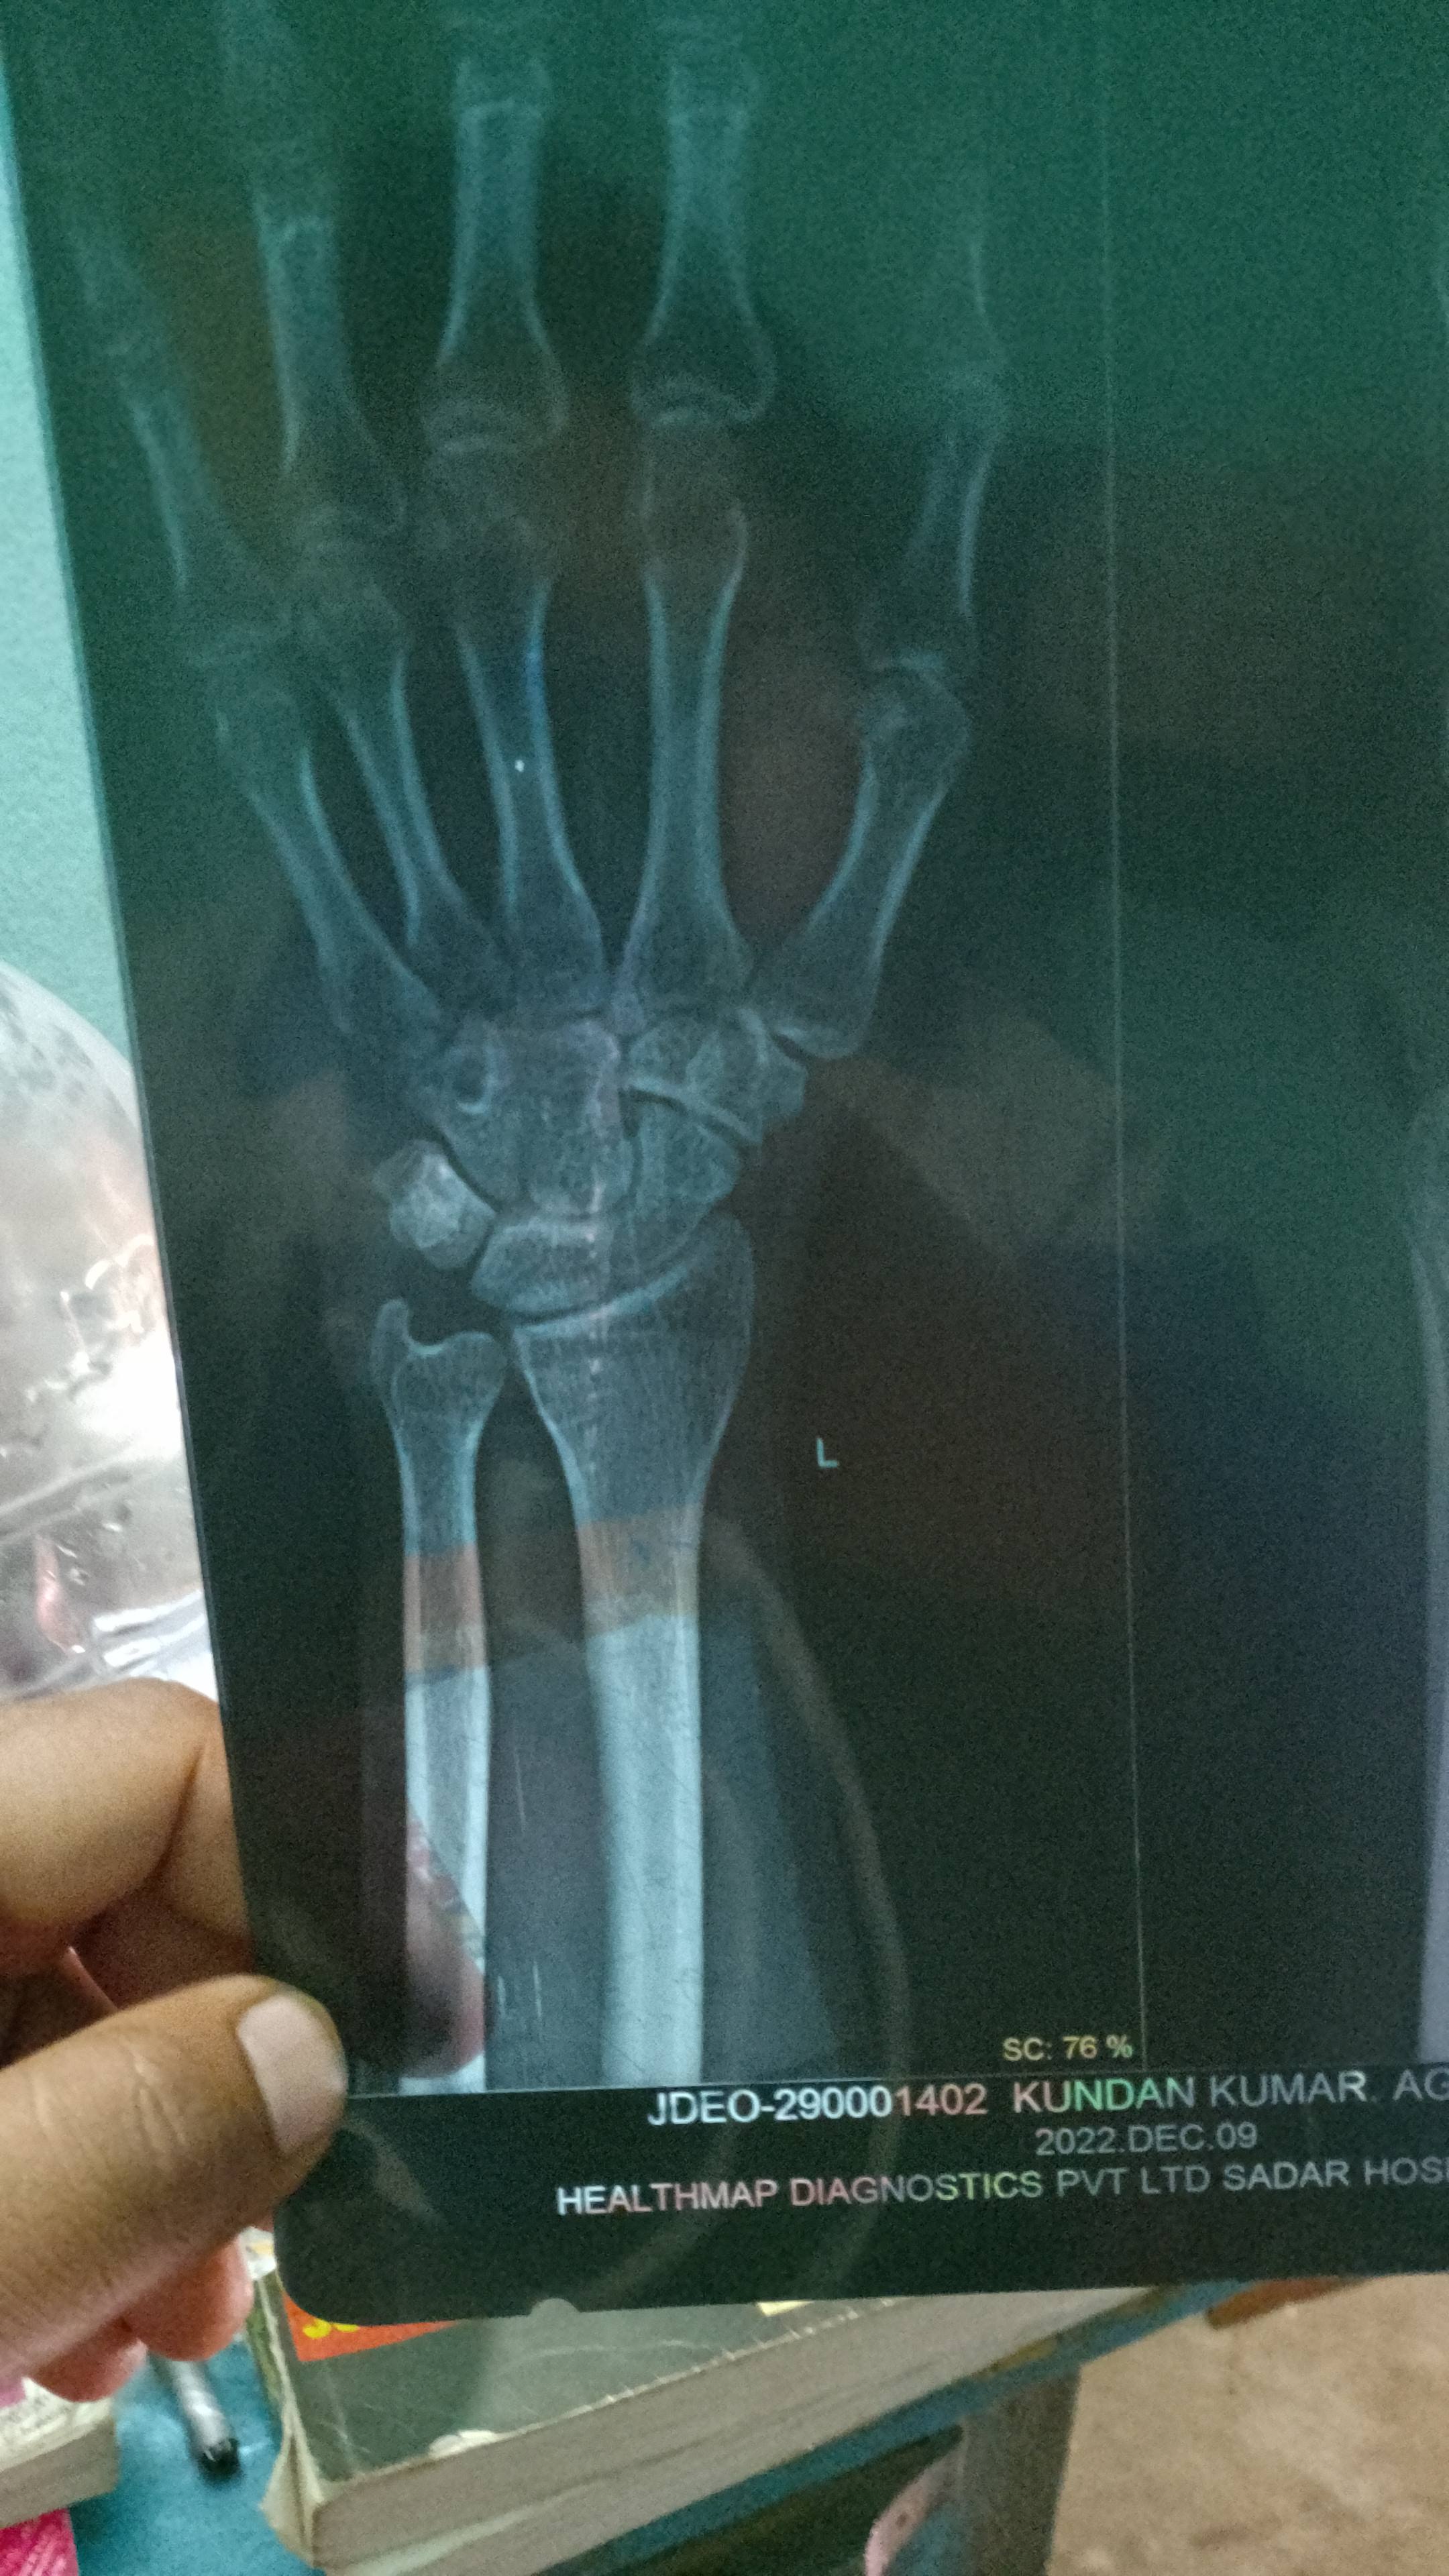

Kundan kumar